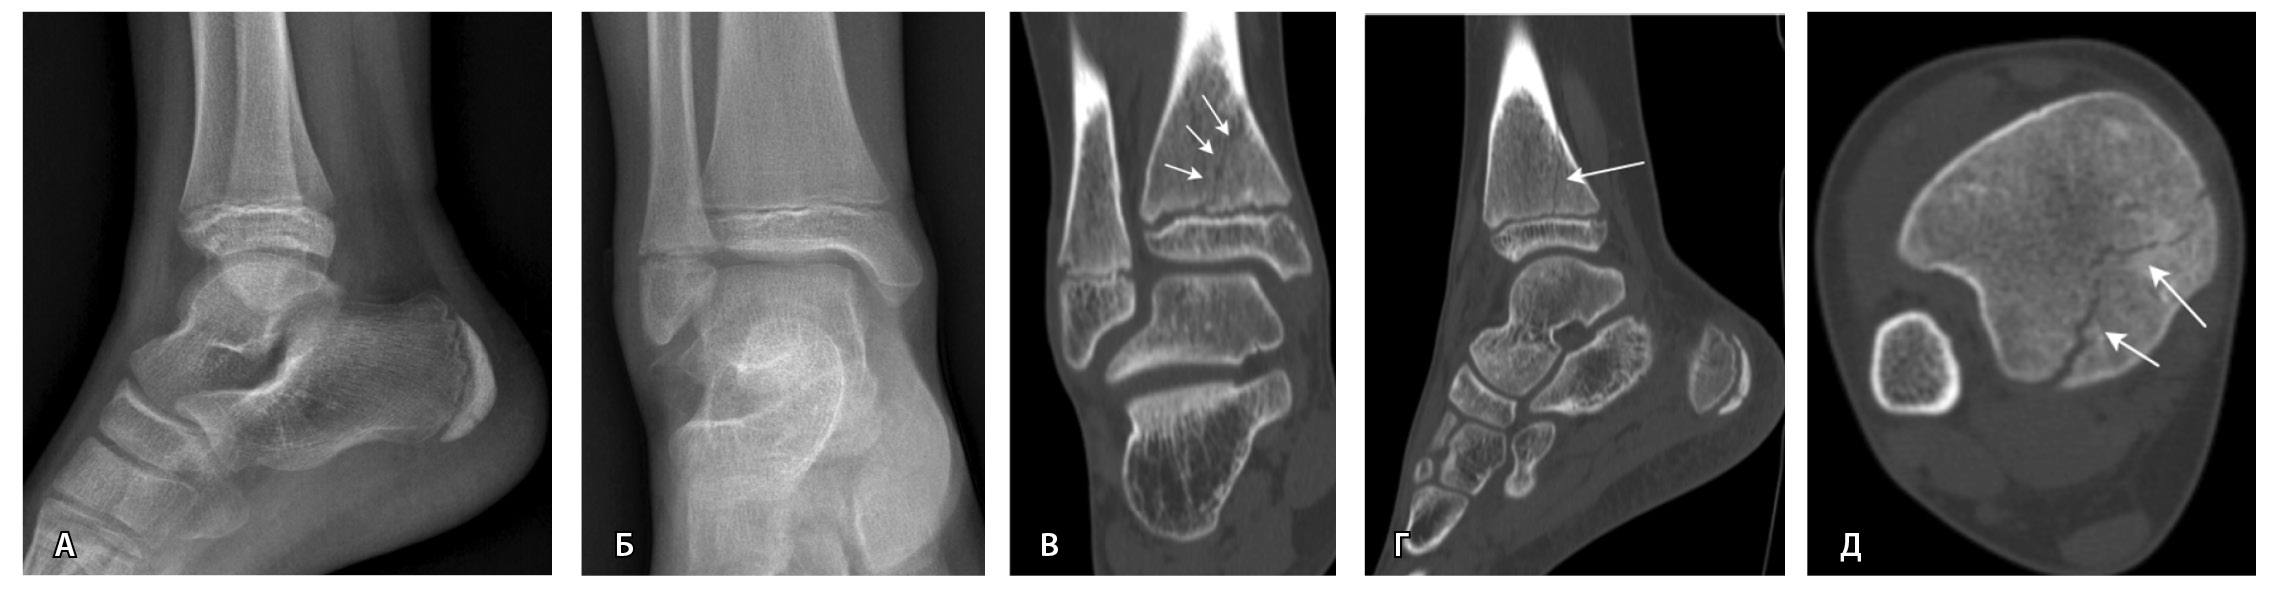

Переломы без смещения фрагментов, а также краевые и авульсионные переломы не всегда четко визуализируются на рентгенограммах из-за суперпозиции теней, наличия фиксирующих шин и гипсовых повязок, которые накладываются на зону интереса. При клинических признаках перелома и рентгеннегативной картине у таких пациентов КТ имеет большую диагностическую значимость (рис. 2).

Рис. 2. Рентгеннегативный перелом дистального метадиафиза большеберцовой кости 2-го типа по Солтеру – Харрису (стрелки) у мальчика 11 лет: А, Б – рентгенография; В – компьютерная томография (КТ), корональная плоскость; Г – КТ, сагиттальная плоскость; Д – КТ, аксиальная плоскость